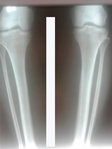

Дата операции 21.03.2018г.

Дата снятия аппаратов 06.07.2018г.

Срок лечения 105 дней.